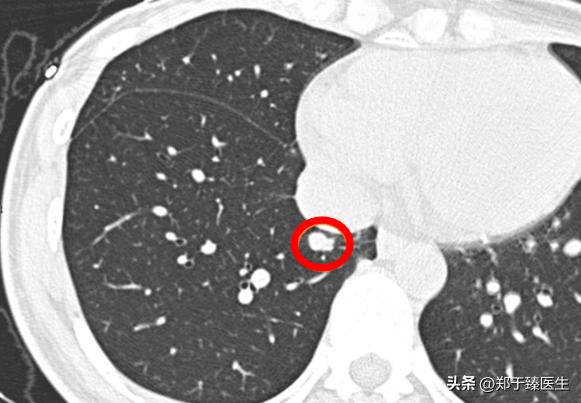

上图是ALK驱动肺腺癌的发展规律。

和EGFR不一样的是,ALK驱动的肺癌绝大多数不会出现磨玻璃阶段,而是直接表现为实性结节。

因为缺乏磨玻璃的保护,使得由ALK突变的肺癌即便体积很小,也具备较强的侵袭性,甚至可能发生淋巴结转移。